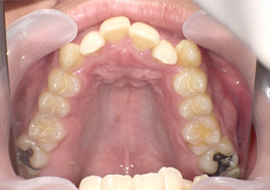

症例3

Before

After

| 主訴 | 上下の歯のガタガタを治したい |

|---|---|

| 年齢 | --- |

| 治療 期間 |

約10ヶ月 |

| 治療 内容 |

インビザラインiGoで上下顎の治療。 狭まっていた歯並びを広げることで、 ガタガタに並んでいた歯を綺麗に並べた。 |

| 治療費 | ¥517,000(税込)+月額調整料 |

| 治療のリスク | 歯と歯の間を削ることでスペースを確保するので、 場合によっては歯が染みる症状が出ることがある。 |